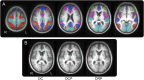

Methods: PD participants without dementia (n = 43) and age-matched controls (n = 22) had lumbar punctures to measure CSF protein levels, Pittsburgh compound B (PiB)-PET imaging, and rs-fcMRI while off medication. Imaging analyses focused on 5 major resting-state networks as well as the striatum.

Results: Participants with PD had significantly reduced sensorimotor functional connectivity, which correlated with reduced CSF levels of α-synuclein. The PD group also had significantly stronger default mode network functional connectivity that did not correlate with CSF β-amyloid (Aβ)42 or PiB uptake. In contrast, default mode network functional connectivity in the control group did correlate with CSF Aβ42 levels. Functional connectivity was similar between groups in the dorsal attention, control, and salience networks.